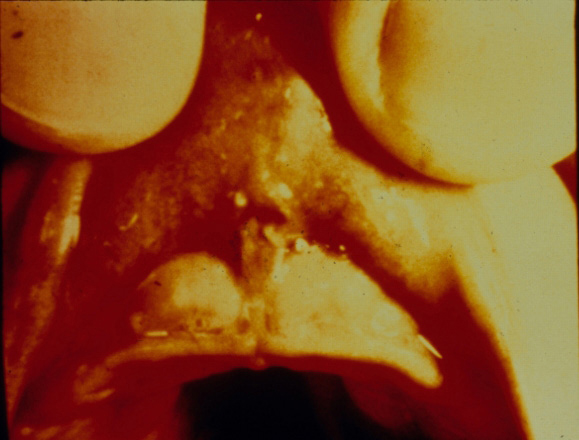

Even cases of child sexual abuse may exhibit indicators in the perioral region. Oral or perioral lesions of gonorrhea, syphilis, or chlamydia in prepuberal children are indicative of sexual abuse.14 In addition, petechiae of the hard or soft palate are sometimes seen in cases of forced oral sex (Figure 8). Other indicators of possible child abuse may include pain or difficulty in walking or sitting, pregnancy in young children, and extreme fear of any dental treatment. Of course, not everyone who is afraid of dental treatment is a victim of child sexual abuse. Because of their history of abuse, however, victims of an oral rape can be terrorized by having something as benign as a mirror or explorer placed in their mouths.

Figure 8. Petechiae of the hard palate resulting from forced oral sex.

Figure 8